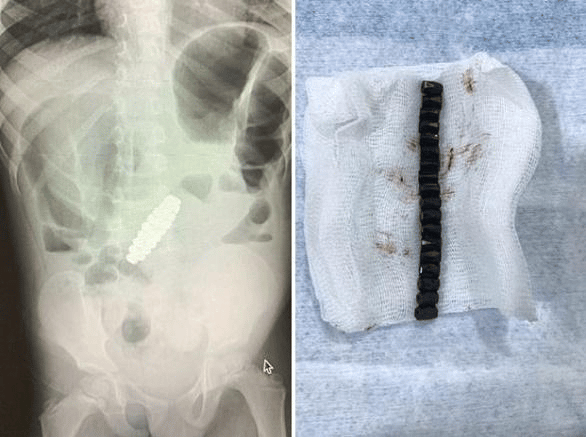

تمكن أطباء أمريكيون من انتشال 18 قطعة مغناطيسية ملتصقة ببعضها البعض من معدة طفل يبلغ من العمر 4 سنوات.

وأصيب الأطباء بالدهشة عندما أخضعوا الطفل للتصوير الشعاعي، وبدا وكأنه يحمل سواراً داخل معدته. وكانوا مندهشين لرؤية شيء على شكل سوار، وكان والداه مرتبكين بنفس القدر، وفقًا لمجلة Paediatric Surgery Case Reports الأمريكية.

ويعتقد الأطباء أن الطفل قد ابتلع كل حبة مغناطيسية على حدة خلال مدة غير معروفة، ولكن بسبب خصائصها المغناطيسية، فقد تمكنت من الالتصاق ببعضها البعض مشكلة حلقة، ووصلت إلى حد سد أمعائه وحتى حفر ثقوب في أمعائه.

وأجرى الجراحون على الفور عملية فتح البطن على الطفل لإزالة 18 قطعة مغناطيسية سداسية الشكل، ثم سارعوا لإصلاح الضرر الذي لحق بأمعائه.